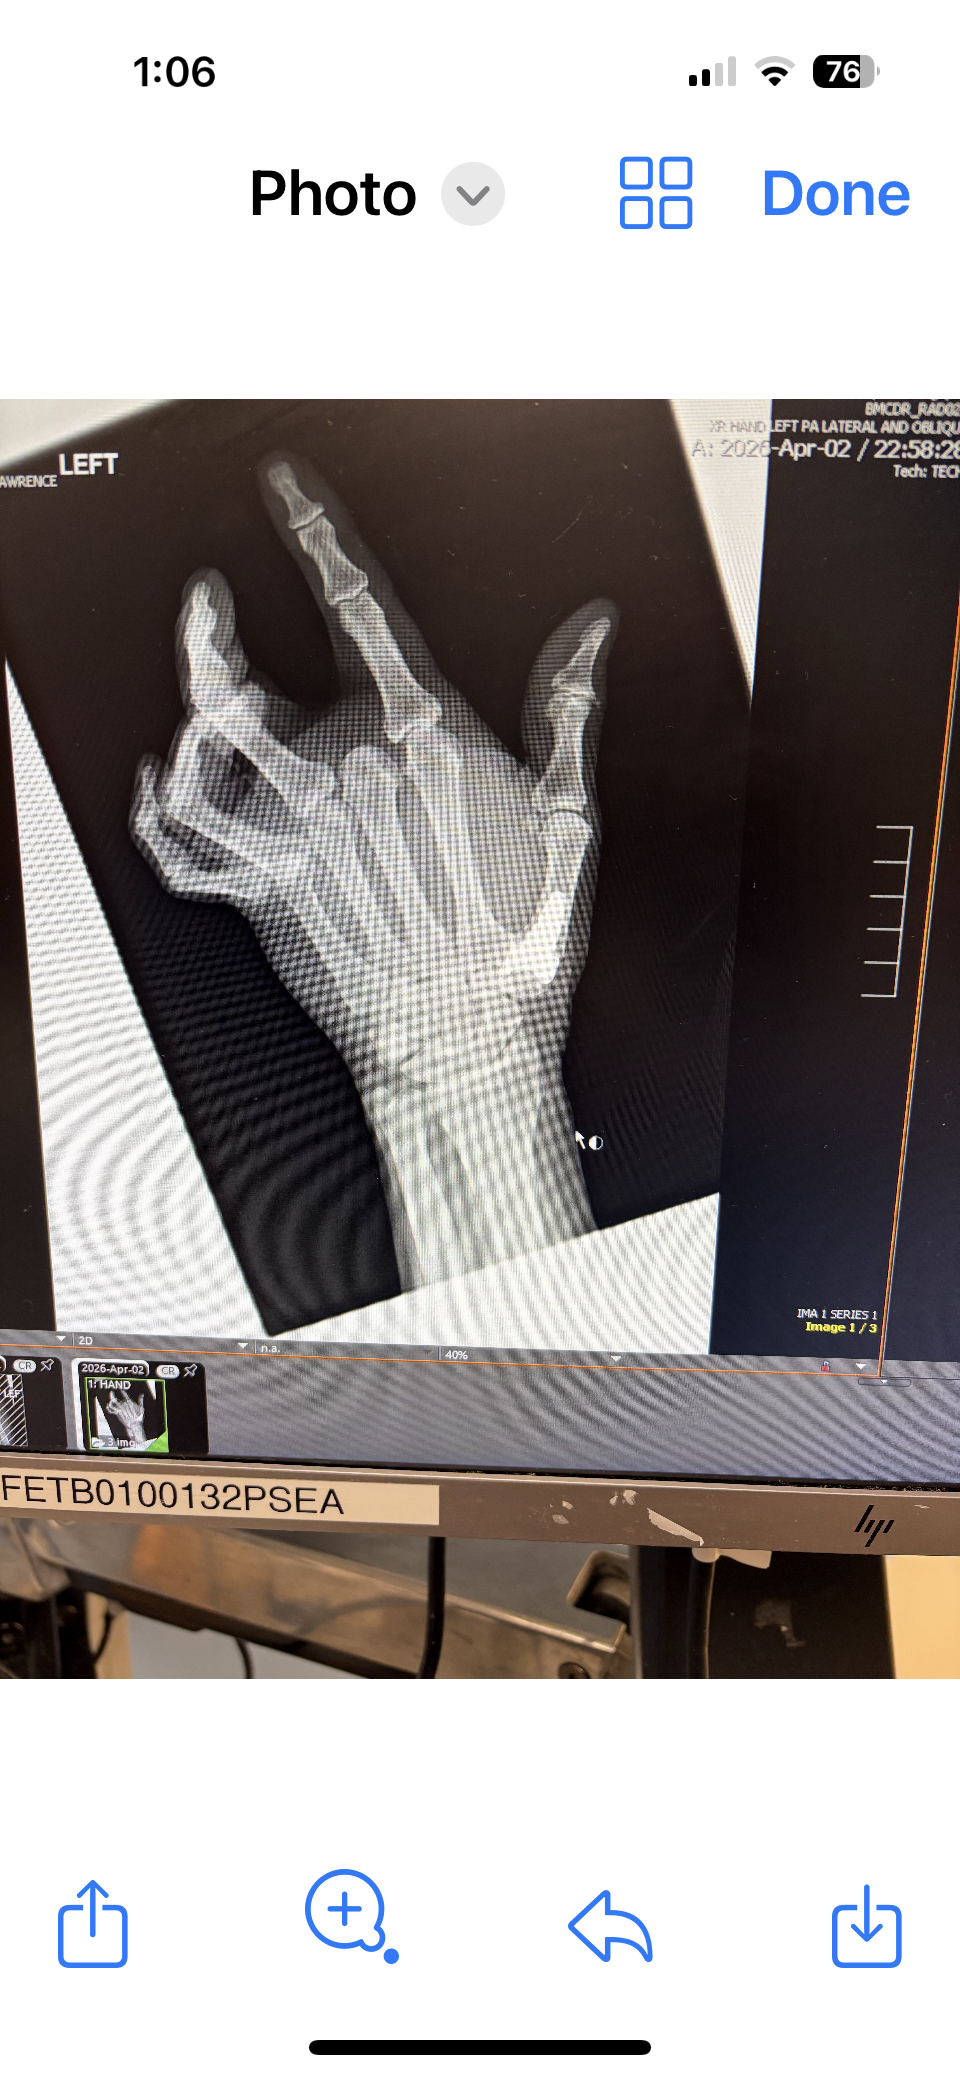

It is Todd! Surprised the tendons etc. weren’t torn! I can wiggle my fingers already! Stitches come out Tuesday, and pins about 2 weeks later I think. Then physical therapy! I urge all 70 year olds to sit on the bed to remove pants to prevent feet from tangling up and falling! Stupid me! Note to self: I am not 30 anymore!

Xray before reconstruction and pins!

Not sure how all the pics of granddaughters showed up! Obviously the last pic is the xray!